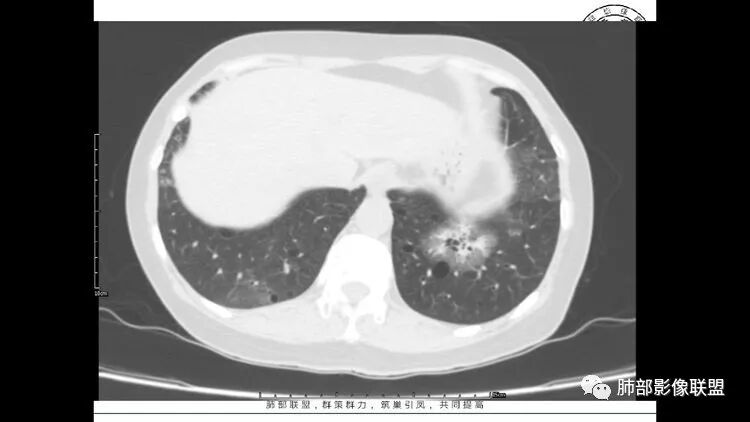

老年女性,眼炎入院,血常规正常,双肺多发囊状影,病变随机分布,形态单一,与血管关系密切,考虑LIP。左下肺混合GGO,边界尚清,贴近囊腔,鉴别腺癌。炎症指标无异常暂不考虑感染性病变。

胸CT:1.双肺多发囊性变,以中下肺为主,病变边缘可见肺动脉,部分囊内可见分隔及肺动脉,双下部分肺野周围可见小叶中心结节及树丫征。

2 左肺上叶尖后段 右肺上叶前段 右肺下叶外基底段 结节影,边界清楚,可见柔软毛刺,左肺下叶后基底段混合密度影。

3.纵隔淋巴结肿大?,以主动脉弓为界向上向下增大。

考虑:淋巴瘤肺浸润,眼部症状考虑与此有关;LIP?;继续鉴别肺腺癌?血管炎?。

双肺下叶分布为主的间质改变(磨玻璃影、小叶间隔增厚)、散在气囊影(常有血管贴边)、边界不清小结节